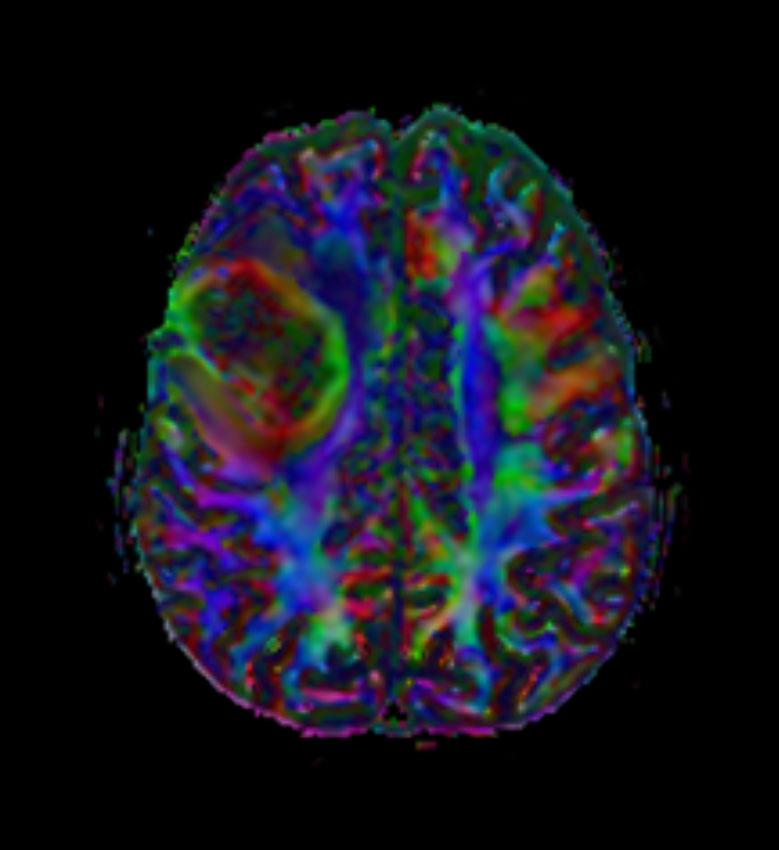

Axial DTI FiberTrak (FA)

-

DTI FiberTrak